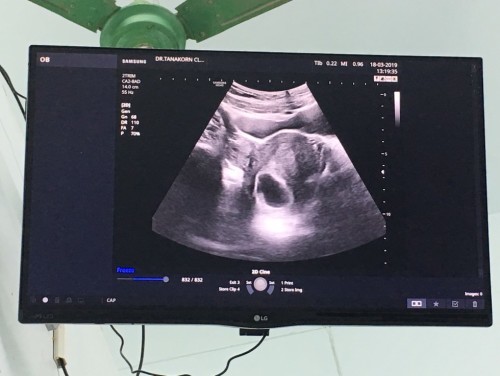

ไปอัลตร้าซาวด์ผ่านหน้าท้องตอน 8 วีค คุณหมอบอกว่าท้องลมค่ะ ตอนนี้ตั้งครรภ์ได้ 9 วีค 6 วันแล้วค่ะ ไม่มีอาการเจ็บท้อง เลือดออก คุณหมอนัดอัลตร้าซาวด์อีกที วันที่ 1 เมษายน 2562 ถ้าไม่เจอตัวเด็กต้องยุติการตั้งครรภ์ (ขอให้ปาฏิหาริย์มีจริงขอให้ลูกยังอยู่และแข็งแรง) เพราะเราท้องมานี่ ท้องที่ 3 แล้ว ไม่สมหวังสักที ?

ลองซาวทางช่องคลอดอาจจะเจอนะคะแม่ เราซาวหน้าท้องไม่เจอแต่เปลี่ยนมาซาวช่อวคลอดเจอ #เป็นกำลังใจให้นะคะ